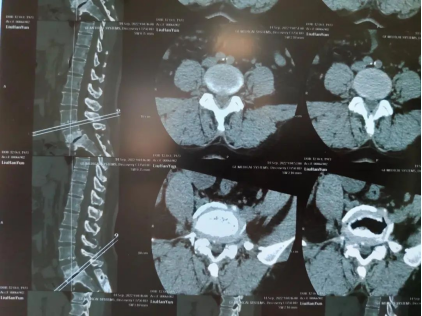

圖一:患者術(shù)前影像資料

48歲的劉女士,已經(jīng)腰痛7年了,長時(shí)間的腰痛導(dǎo)致她雙腳疼痛、麻木,影響日常勞作及睡眠,嚴(yán)重影響生活質(zhì)量。她輾轉(zhuǎn)多家醫(yī)院就診無果后,了解到臨沂市第三人民醫(yī)院疼痛科已經(jīng)開展OSE脊柱內(nèi)鏡下經(jīng)后入路手術(shù),于2022年9月14日入住疼痛科就診,完善相關(guān)檢查。許成君主任診斷為:腰椎滑脫、腰椎間盤突出伴椎管狹窄。要治愈該癥狀,傳統(tǒng)手術(shù)需要開放手術(shù),不僅創(chuàng)傷大,而且風(fēng)險(xiǎn)高,稍有不慎,就會(huì)導(dǎo)致患者癱瘓。在疼痛科醫(yī)療團(tuán)隊(duì)的詳細(xì)檢查和評(píng)估后,考慮到患者的實(shí)際需求,制定了詳實(shí)的手術(shù)治療方案,與患者及家屬術(shù)前多次充分溝通并取得同意后,決定為患者實(shí)施單通道(OSE)下行L5/S1椎板開窗減壓+髓核摘除+神經(jīng)根松解+盤內(nèi)植骨融合術(shù)。經(jīng)過充分的術(shù)前準(zhǔn)備,9月18日,在手術(shù)室和麻醉團(tuán)隊(duì)的全力配合下,許成君主任在C臂透視下,在腰5棘突右側(cè)旁開2CM小口,植入OSE內(nèi)鏡和操作器械,在術(shù)中可視下成分處理椎間隙中變性髓核組織,滑脫腰5椎體進(jìn)行復(fù)位,椎間植骨融合、釘棒系統(tǒng)內(nèi)固定。手術(shù)出血約100ml,術(shù)后效果滿意,癥狀緩解明顯。